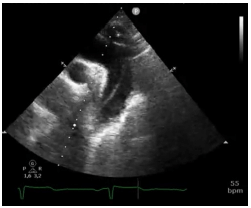

Analise a figura a seguir.

Em relação à figura acima, assinale a opção que indica a condição patológica evidenciada.